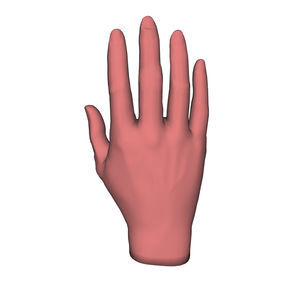

Anatomisches Modell / Schulter HUM-Efür Punktionenfür Injektionenfür Ultraschalluntersuchungen

- Anatomisches Modell / Hand

- Anatomisches Modell / Handgelenk